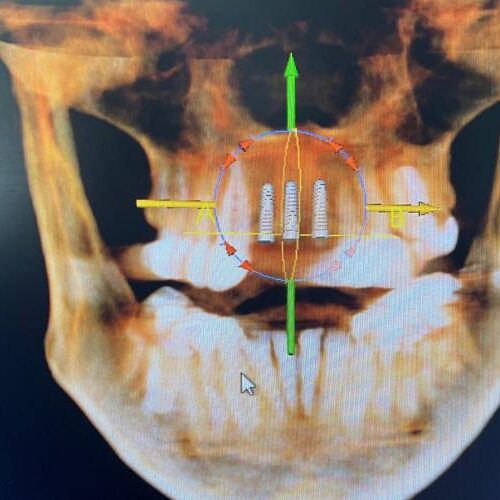

Advanced dental implants delivered by expert Oral and Maxillofacial Surgeons, combining precision surgery with compassionate care. We offer sedation options for comfort, along with wisdom teeth removal, extractions, and bone grafting surgery. Every procedure is performed with a surgeon-led approach focused on safety, function, and long-term results for patients care.